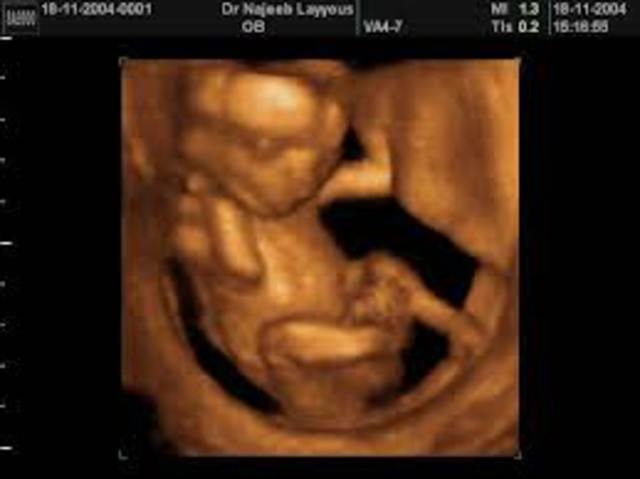

• Month 5 week 18-21

Month 5 week 18-21

The baby is now 15-16 cm long, and weighs around 200 gm.The baby is moving all around your uterus, and you may feel these movements.